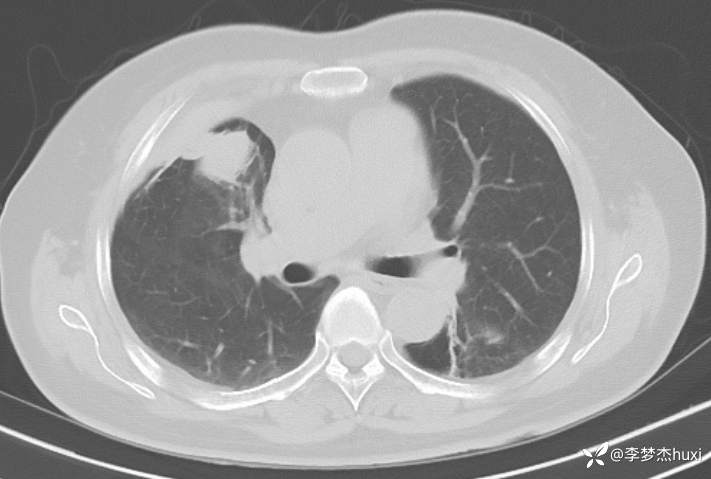

女性69岁,胸痛住院,检查发现肺占位性病变,猜病理

辅助检查:胸部CT:右肺占位?炎症?双肺炎性变,左肺下叶陈旧性病变,双肺纹理增多,主动脉及冠状动脉钙化,双侧胸膜局部增厚,胆囊结石,多发肝囊肿?请结合超声。

临床诊断:肺占位